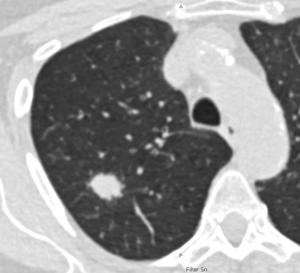

IMAGE: Lung CT © Charité | Jens Vogel Claussen

Image: Low-dose CT scan of the lungs of a 69-year-old female smoker. The white, rounded area in the lung tissue indicates early-stage lung cancer. At this stage, lung cancer is still highly treatable. © Charité | Jens Vogel-Claussen